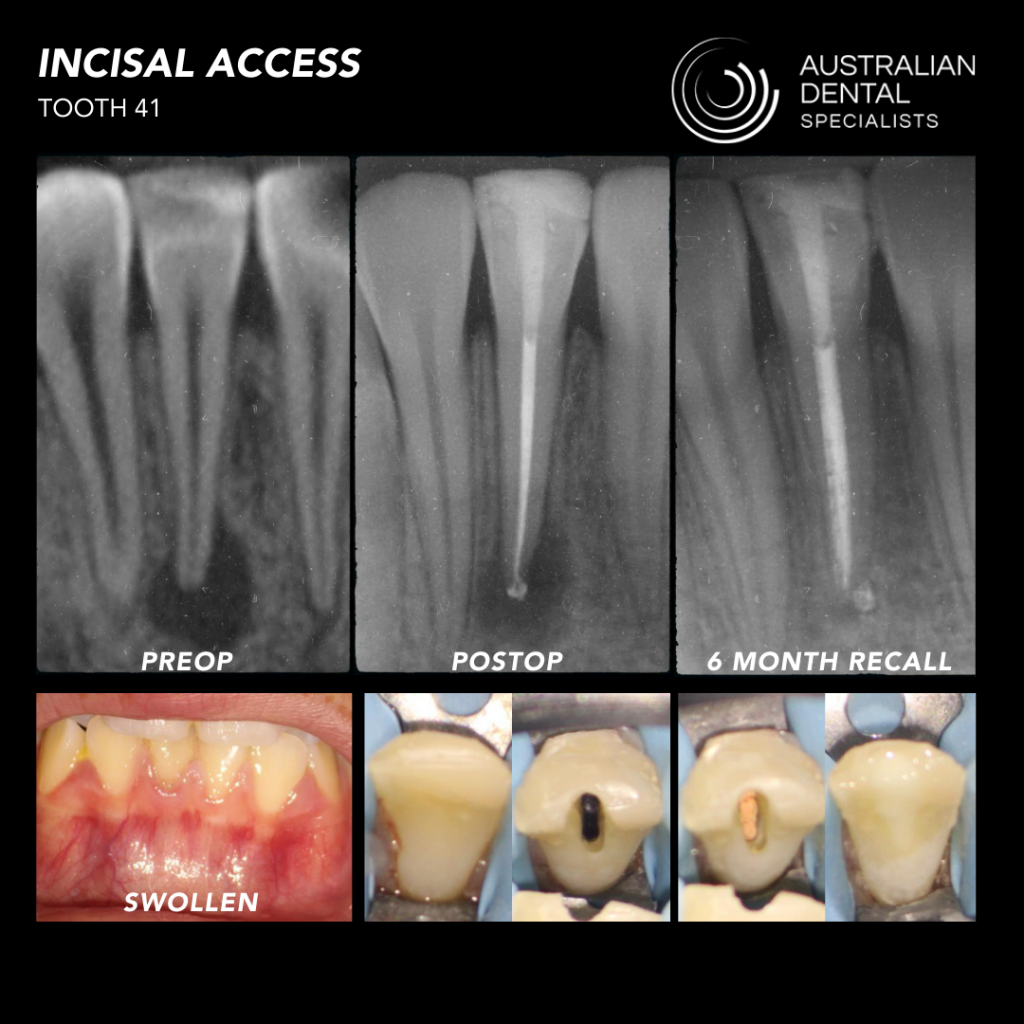

After that, the recall appointments started coming in, and the radiological healing was quick and comparable to those I had treated in multiple visits in the past. Over the last 18 months of practice, I’ve utilized the Waterlase on every single case that comes into my office. It’s so versatile that I can also use it for access preparation, cleaning sinus tracts, gingival augmentation, and crown lengthening.